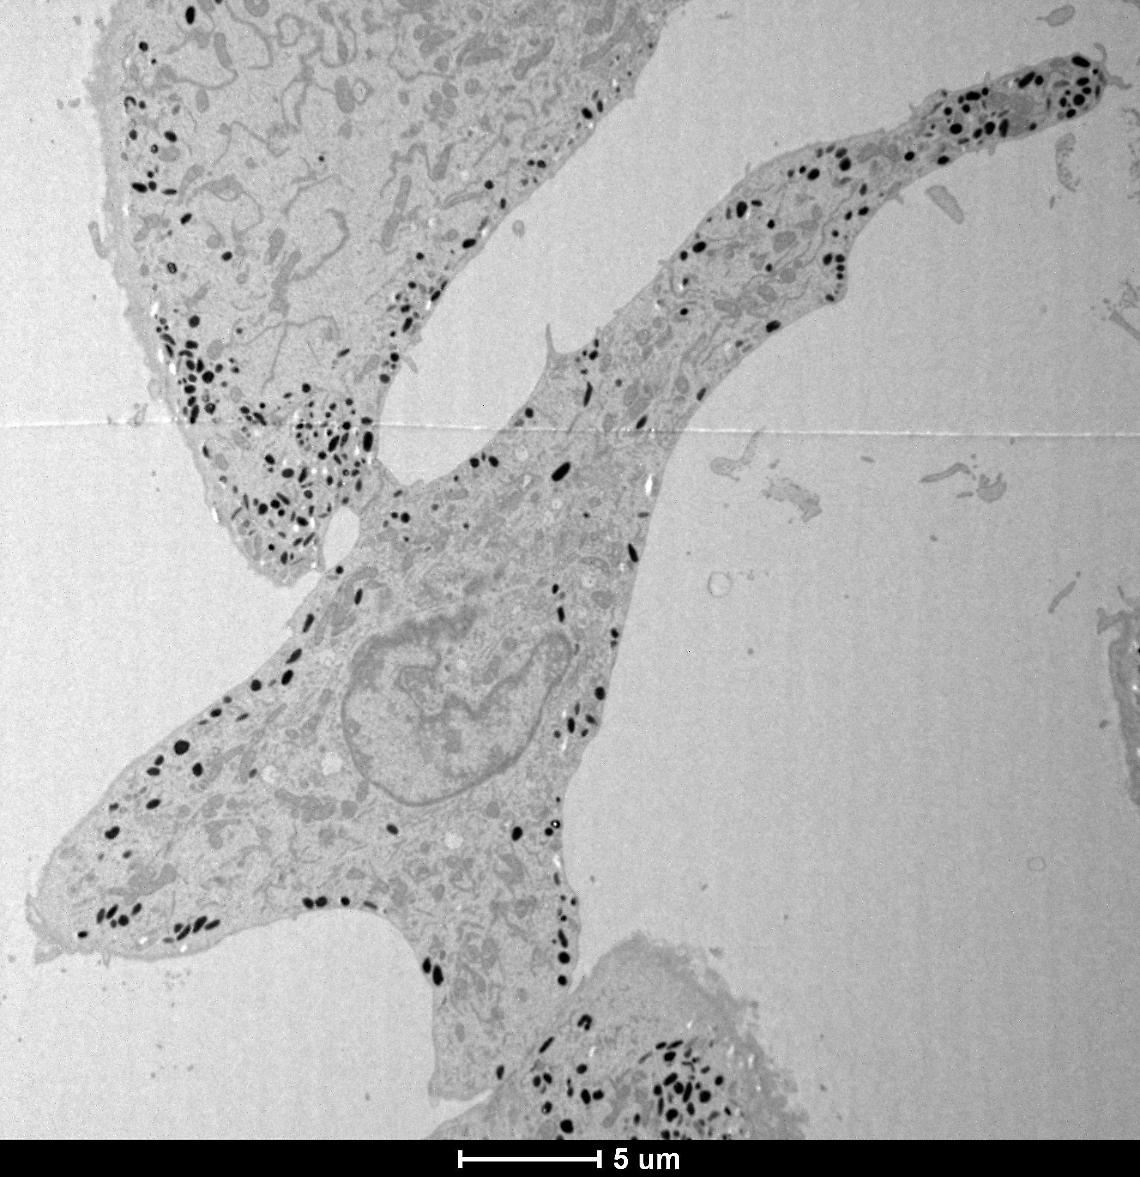

I melanosomi, le piccole “fabbriche” cellulari che producono melanina per colore di pelle, capelli e occhi, hanno un nuovo regista: MFF. Uno studio dell’Università di Padova, pubblicato su Nature Communications, ha rivelato che questa proteina, già nota per la sua funzione nei mitocondri, controlla anche la forma e la maturazione dei melanosomi, in modo del tutto indipendente dal suo partner abituale DRP1.

La ricerca, finanziata dalla LEO Foundation, ha mostrato che MFF si trova sulla superficie dei melanosomi nei punti in cui questi ultimi si preparano a dividersi. Riducendo la produzione di MFF nei melanociti, i ricercatori hanno osservato melanosomi più grandi e un accumulo di melanina, con alterazioni nei processi di pulizia interna dell’organello. Curiosamente, DRP1 non produceva lo stesso effetto, confermando che MFF agisce sui melanosomi in maniera autonoma.

Il meccanismo individuato dai ricercatori padovani è sorprendente: MFF può trasferirsi dai mitocondri ai melanosomi tramite vescicole, localizzandosi nei punti di divisione dove collabora con filamenti di actina e il complesso proteico ARP2/3. Questo favorisce il restringimento delle membrane e la separazione dei melanosomi, consentendo loro di eliminare il materiale in eccesso.